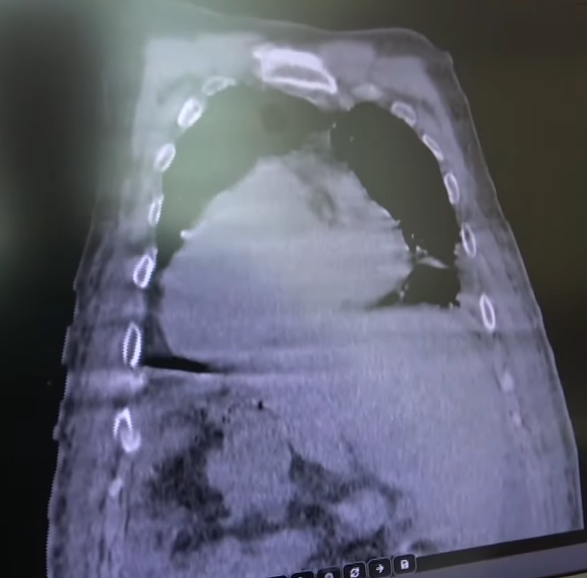

Kaydedilen ilk vakada transtorasik ekokardiyografide, biatriyal dilatasyon ve orta derecede triküspit dilatasyonu ile birlikte dekstrokardi ve sol ventrikül ejeksiyon fraksiyonunun %35'i saptanmıştır. Karın ultrasonografisi karaciğerin sol üst kadranda ve dalağın sağ üst kadranda yer alarak karaciğer ve dalağın ters yerleşimli olduğunu göstermiştir. Akciğer grafisi hafif kardiyomegali, dekstrokardi ve bilateral plevral effüzyonları ortaya koymuştur. Parasentez ile orta derecede asit saptanmış, serum-asit albumin gradiyenti (SAAG) 1.4 mg/dL ve toplam protein 4.6 mg/dL olarak ölçülmüştür. Nötrofil seviyelerinde peritonit bulgusu gözlenmemiştir. Laboratuvar ve radyolojik veriler ışığında kardiyak asit tanısı doğrulanmıştır.

Giresun Sendromunda Gövdenin Görüntülenmesi (YouTube)